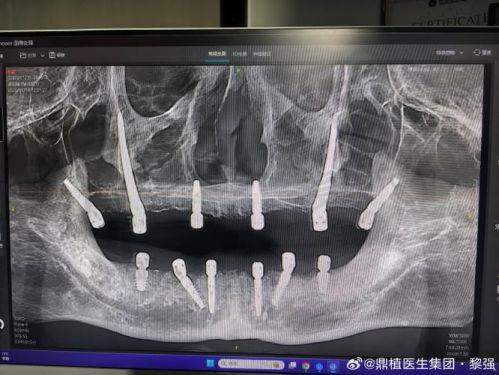

穿颧穿翼半口种植牙是一种针对重度骨量缺失患者的高端种植技术。传统的种植牙技术需要患者有足够的牙槽骨骨量来支撑种植体,但对于一些因长期缺牙、外伤等原因导致牙槽骨重度吸收的患者来说,传统种植往往难以实施。而穿颧穿翼种植牙技术则突破了这一限制,它通过将种植体植入颧骨或翼板等骨量充足的部位,为种植体提供稳定的支撑,从而实现半口牙齿的修复。